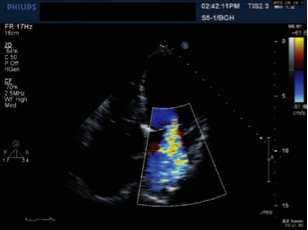

Echocardiography and Doppler

ALL patients: Trans-thoracic echocardiography with Doppler; determine left and right ventricular function and pulmonary artery pressures